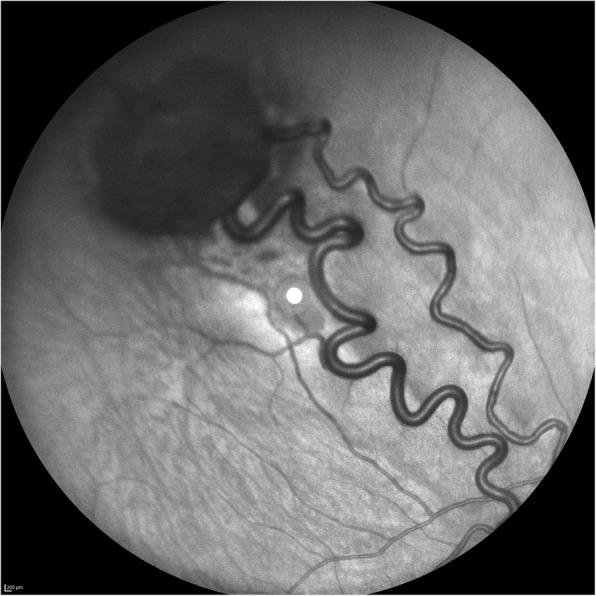

Detection of retinal microvascular changes in von Hippel-Lindau disease using optical coherence tomography angiography.

PLoS One. 2020 Feb 20;15(2):e0229213. doi: 10.1371/journal.pone.0229213. eCollection 2020.

Value of Optical Coherence Tomography Angiography Imaging in Diagnosis and Treatment of Hemangioblastomas in von Hippel-Lindau Disease.

Ophthalmic Surg Lasers Imaging Retina. 2016 Oct 1;47(10):935-946. doi: 10.3928/23258160-20161004-07.